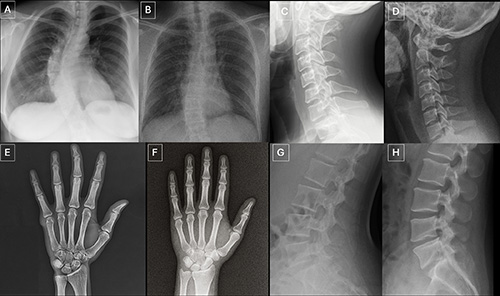

Images (JPG, TIF):

Figure 4. Examples of GPT-4o-generated radiographs of fractures: (A) posteroanterior radiograph of the hand, (B) posteroanterior radiograph of the lower leg, and (C) medial oblique radiograph of the foot. The images show fracture lines (arrow) that are unusually smooth, clean, and consistent and, in the case of B, unicortical. The presence of these idealized fracture lines, characterized by unnatural smoothness and incomplete cortical disruption, could serve as a primary diagnostic cue for identifying artificial intelligence–generated trauma images.